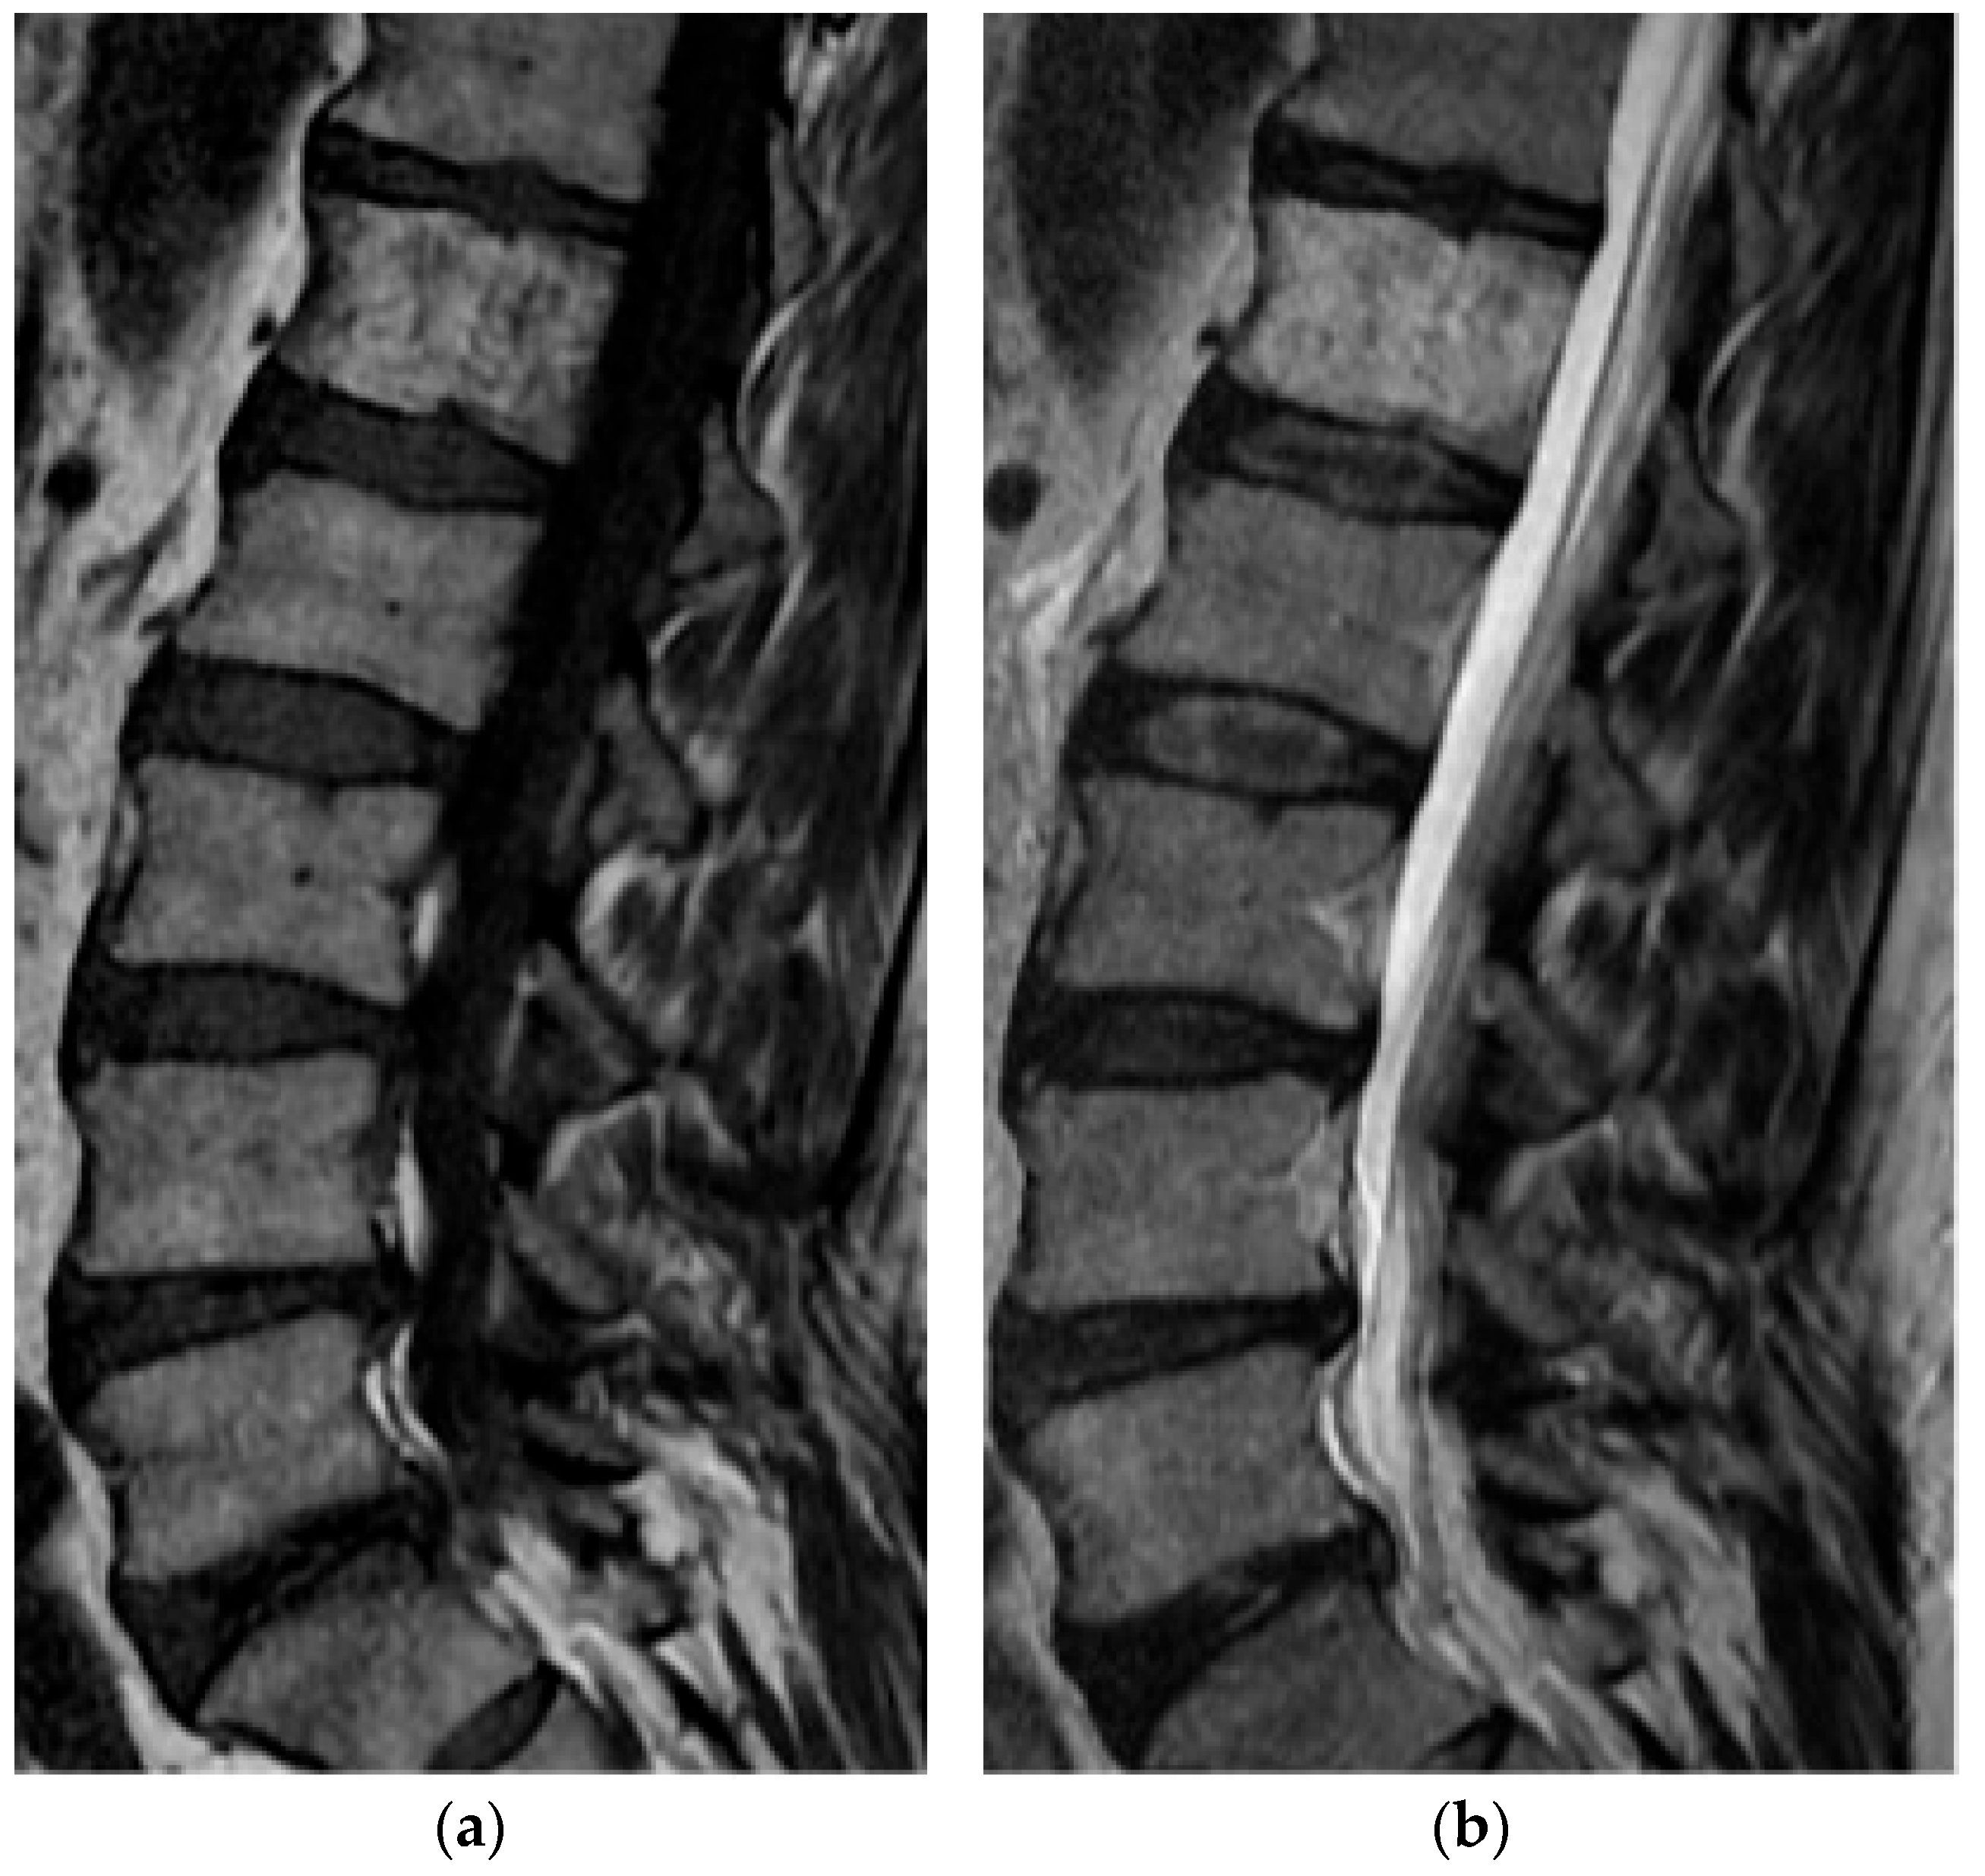

2.5.1. Hemangioma

2.5.2. Aneurysmal Bone Cyst